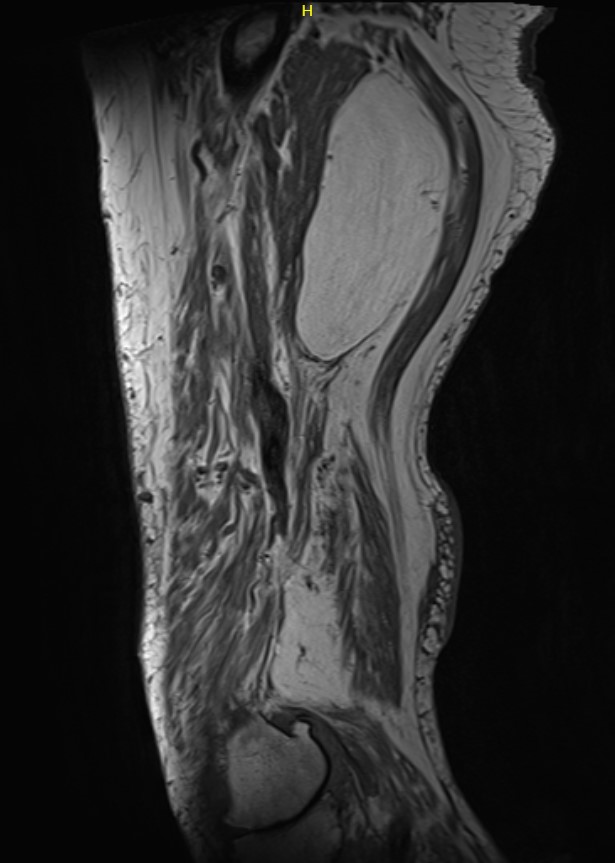

Liposarcoma

MRI

Deep to fascia / heterogenous

Liposarcoma posterior thigh

LS 3LS 2LS 1